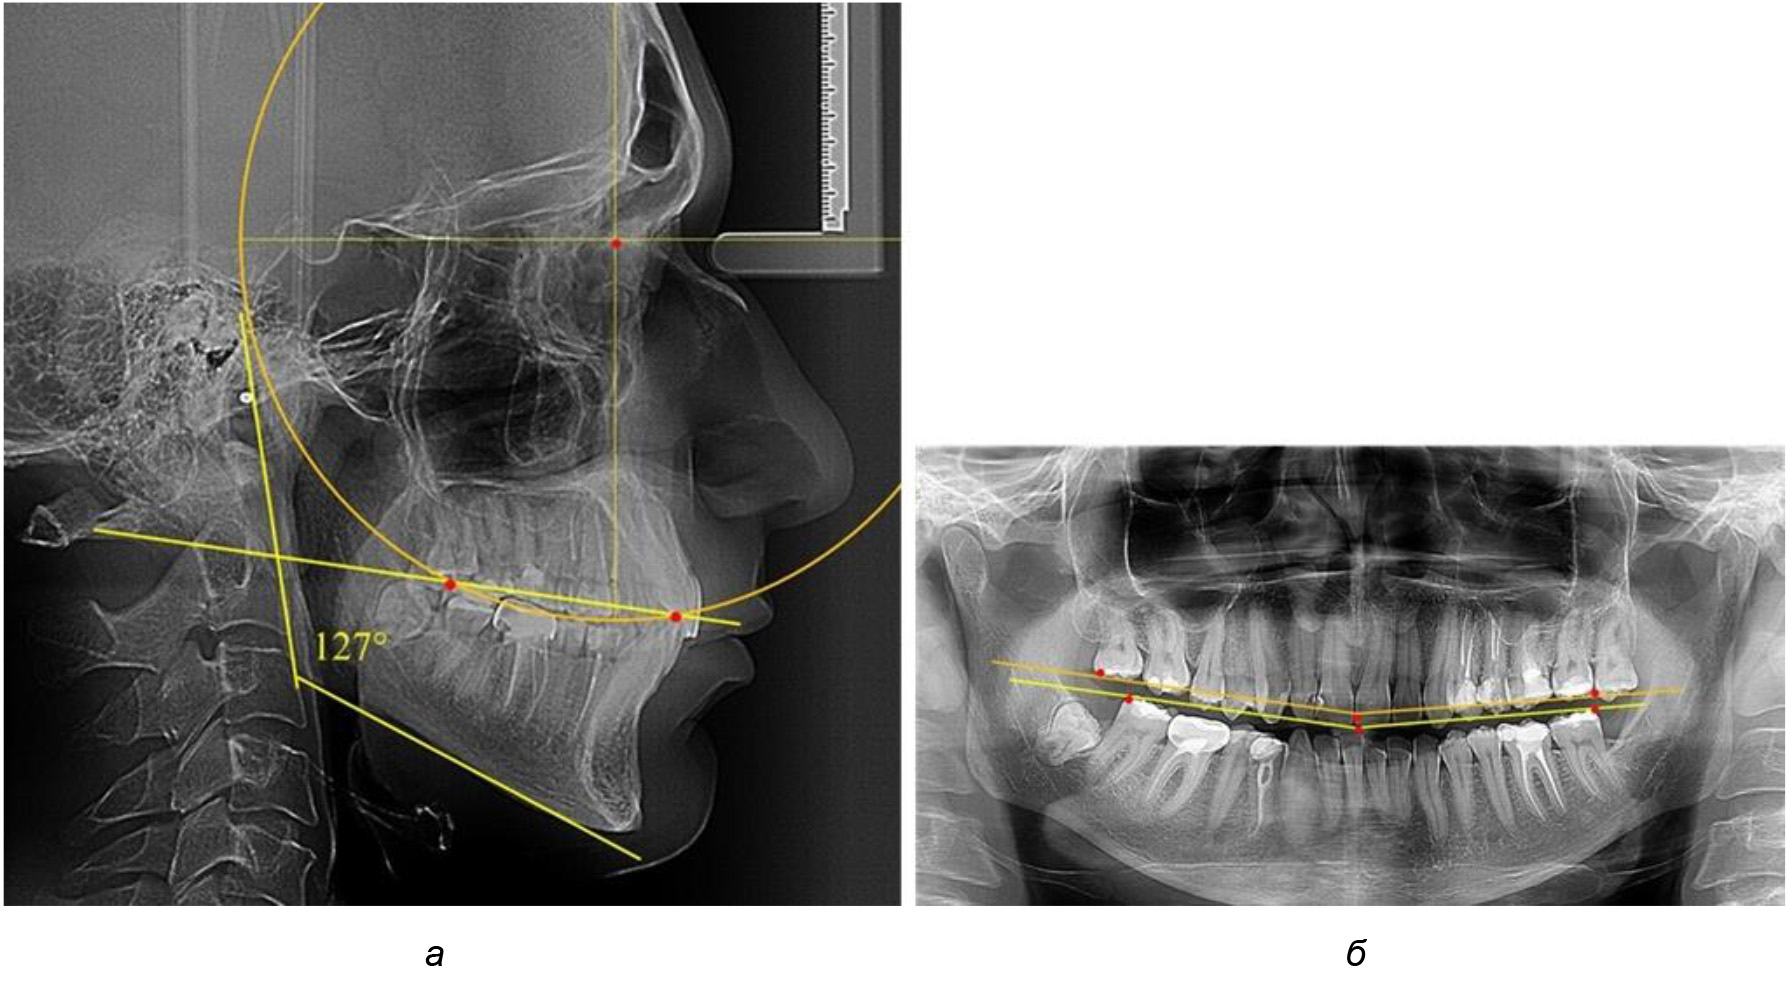

Рис. 2. Особенности кривой Spee на ТРГ (а) и ОПТГ (б) у людей с признаками вертикального роста

Рис. 3. Особенности кривой Spee на ТРГ (а) и ОПТГ (б) при нейтральном типе роста нижней челюсти

Рис. 4. Особенности кривой Spee на ТРГ (а) и ОПТГ (б) у людей с горизонтальным типом лица

Деление величины радиуса круга к длине окклюзионной линии составило 1,623 ± 0,02. Таким образом, для определения радиуса окружности, соответствующей кривизне окклюзионного контура боковой ТРГ, необходимо измерить расстояние между передней и задней окклюзионными точками и последующим умножением полученной величины на число Фибоначчи (рис. 2).

Достоверных различий с показателями, полученными при анализе ТРГ и ОПТГ, нами не отмечено (р ˃ 0,05). Деление величины радиуса круга к длине окклюзионной линии составило 1,612 ± 0,02, что, так же как и в 1-й подгруппе, было близким по значению к числу Фибоначчи (1, 618).

Глубина кривой Spee в среднем по 2-й подгруппе составил (2,94 ± 0,47) мм, что было меньше, чем в других подгруппах. Деление величины радиуса круга к длине окклюзионной линии составило 1,616 ± 0,02 (рис. 4).